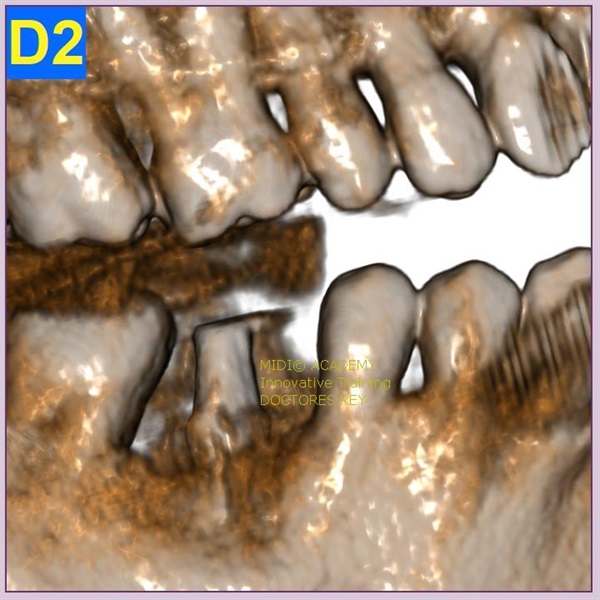

2-Implantes monobloque, en maxilar inferior. MIDI® TECHNIQUE® -US.

4x11,5. colocados con técnica ultarasónica MIDI®, hueso de calidad baja.